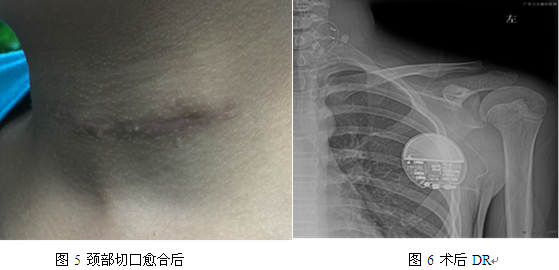

经我院癫痫中心讨论后考虑患者药物难治性癫痫诊断明确,病因为病毒性脑炎后遗症期,考虑患者为双侧多灶癫痫起源,无法行癫痫灶切除手术,但患者可以考虑行迷走神经刺激术,经和患者及其家属详细沟通后,患者及其家属同意行迷走神经刺激术,遂于2016年7月21日全麻行迷走神经刺激器植入术(图3、图4、图5、图6),术后恢复良好,无癫痫发作。